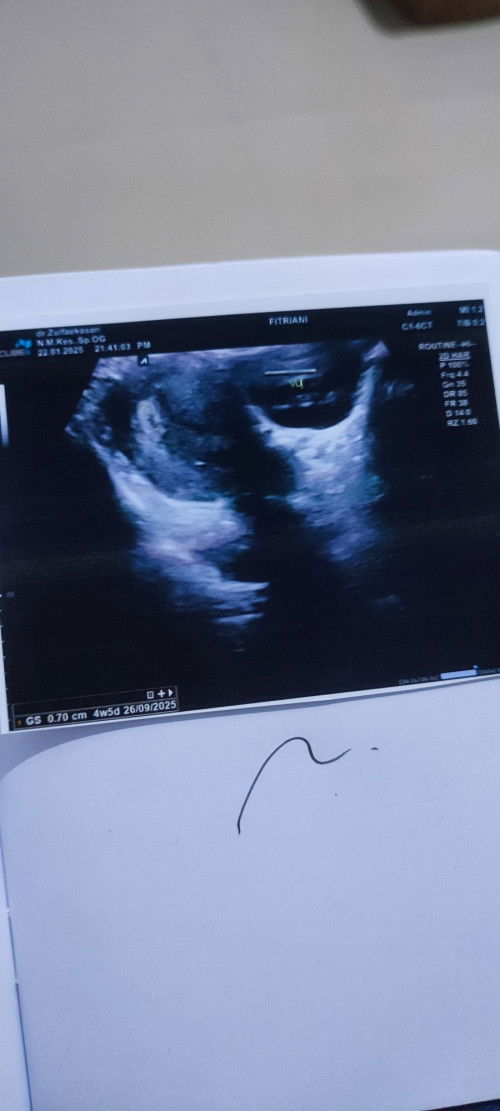

4W5D hasil USG kantong dan Janin sudah kelihatan tapi Janin PEYANGđ„ș

Disini ada gak yah bunda2 sama dengan hasil USG ku, kata Dokter ku janin ku Peyang dan disuruh istirahat total 2 minggu, manatau Bunda-bunda juga punya Solusi atau sarannyađ„șđ#Sharingdong_Bund #mohonbantujawabbunda #bantujawab #firstmom #sharing